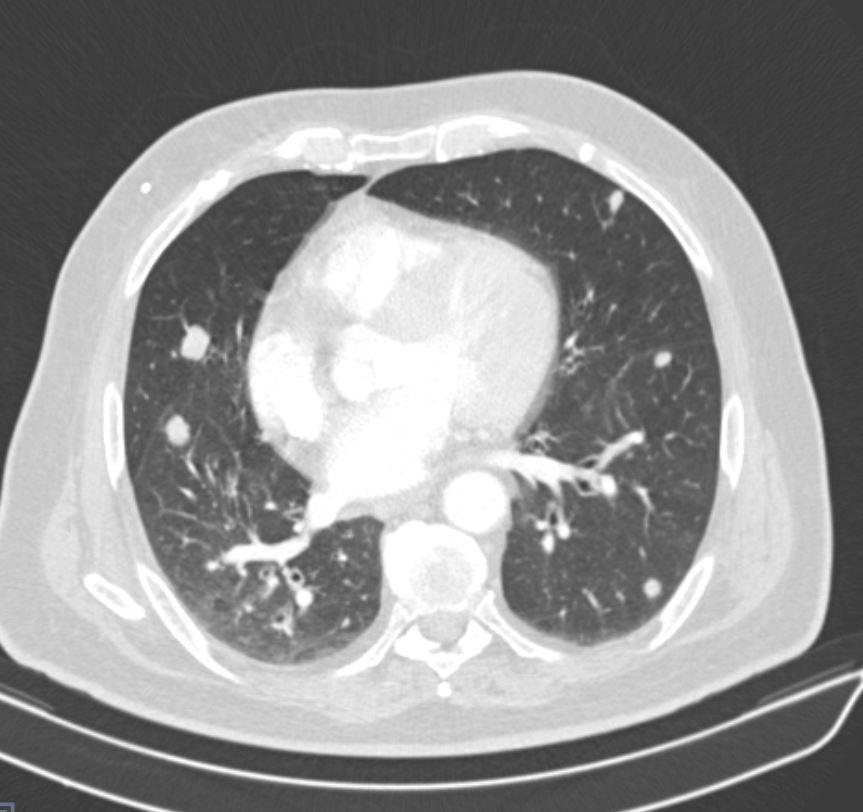

Case of the Week 25 2017 *57-year-old male. What is the most likely diagnosis? Answer Answer: Non-mucinous bronchoalveolar carcinoma and bilateral metastatic pulmonary nodules Kategori:Cases Önceki yazı Case of the Week 24 2017 Sonraki yazı Case of the Week 28 2017